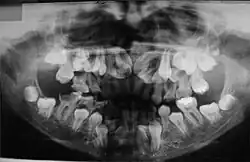

O diagnóstico do portador de DCC é realizado através de exames clínicos e radiográficos. A aparência clínica dos acometidos é bastante característica, principalmente após a puberdade devido a alguns traços dessa doença, como baixa estatura, falha na erupção dos dentes permanentes, dentes supranumerários e retardo na esfoliação dos dentes decíduos. Outros aspectos dessa patologia são: a aplasia ou hipoplasia clavicular (clavículas rudimentares ou completamente ausentes), que está presente em 10% dos casos, que permite o movimento do braço até ao plano sagital mediano. A abóboda craniana aumentada, uma menor espessura do músculo masseter, hipodesenvolvimento do terço médio da face, geralmente também é apresentado uma hipoplasia da maxila, retardo no desenvolvimento esquelético, o pescoço largo e atraso no fechamento das suturas cranianas. Em alguns casos é possível observar que os palatos estreitos e profundos também são frequentes. É importante realizar o diagnóstico diferencial devido aos pacientes exibirem nanismo, ossos densos, frágeis e agenesias parciais das falanges dos dedos dos pés e mãos.[9][10]

Quanto aos dentes dos portadores de disostose cleidocraniana, podem se relacionar anodontia parcial, dentes supranumerários (os quais impedem o desenvolvimento dos dentes permanentes e obstruem a erupção destes dentes), dentes não irrompidos associados a cistos ou tumores odontogênicos, retenção de dentes decíduos (com reabsorção radicular), erupções retardadas pela diminuição do potencial eruptivo, retardo na erupção dos primeiros molares e anomalias da forma dentária (tanto das raízes como presença de dentes conóides). Também alterações do palato são encontradas nesses pacientes, como palato alto, estreito, arqueado e uma prevalência maior das fendas palatinas.[11]

O atraso na erupção dos dentes pode ser explicado pelo aumento na densidade óssea de algumas regiões dos maxilares, em decorrência de uma remodelação anormal do osso; ausência ou diminuição do cemento celular; aumento da espessura da fibromucosa; presença de dentes supranumerários; formação incompleta da lâmina dentária e ausência de rizólise dos dentes decíduos. Jensen e Kreiborg (1993a, 1993b) têm relatado anormalidades morfológicas na maxila e mandíbula destes pacientes. Na maxila, os seios paranasais podem estar pequenos ou ausentes. Na mandíbula, os ramos ascendentes apresentam-se paralelos entre si e os processos coronóides mostram uma curvatura para a distal, além da persistência da sínfise mandibular. Também na face, os ossos nasais são hipoplásicos ou ausentes e os zigomáticos, hipoplásicos.

No estudo realizado por McNamara et al. (1999) sobre as características da síndrome, encontradas nas radiografias panorâmicas, citam-se a presença de múltiplos dentes não irrompidos; dentes com alterações de forma; ramos ascendentes da mandíbula delgados com os bordos posterior e anterior paralelos e, em alguns casos, estreitando-se em direção ao processo coronóide e côndilo; processo coronóide frequentemente ascendente e para posterior; arco zigomático estreito com severa inclinação descendente e algumas vezes descontínuo com a sutura zigomático-temporal; seios maxilares pequenos ou ausentes; bordo infraorbital mais baixo que o normal em relação aos dentes; inclinação descendente do assoalho da fossa nasal em relação à espinha nasal anterior, acentuando a forma em V; trabeculado ósseo da mandíbula com aspecto grosseiro; aumento da densidade da crista óssea alveolar, comprometendo a irrupção dentária; aumento da densidade do ramo ascendente entre o bordo anterior da mandíbula e o canal dentário inferior. A maior parte dos pacientes com disostose cleidocraniana desempenha suas funções normais, não apresentando comprometimento significativo. Existem relatos de que o tratamento cirúrgico com a exposição dos dentes inclusos, combinado com o tratamento ortodôntico, tem sido bem-sucedido em alguns casos (McDONALD, 2001). Porém, a extração dos dentes decíduos não promove a erupção dos dentes permanentes inclusos.[11]

Sabe-se que a retenção prolongada dos dentes decíduos, agenesias e dentes supranumerários provocam má oclusão. Portanto, procedimentos ortodônticos devem ser utilizados com a finalidade de adequar a cavidade bucal para futura reabilitação protética. Os exames radiográficos, além de auxiliar na detecção das anormalidades maxilofaciais, permitem o acompanhamento dos pacientes, sendo, por isso, considerados uma ferramenta para o diagnóstico e conduta terapêutica.[11]

As anomalias orais causadas pela disostose cleidocrania são marcantes, e geralmente, são fatores determinantes para o diagnóstico da DCC, tornando o cirurgião-dentista parte crucial para a descoberta da doença.[12] Estas anormalidades apresentadas pelos pacientes que possuem disostose são numerosas e estão presentes principalmente na dentição decídua, mas também podem aparecer na permanente. São elas: Anodontia parcial (ausência do elemento dentário), dentes supranumerários, erupções tardias, dentição ectópica (fora do local adequado) e anomalias dentárias, palato alto, estreito e arqueado, assim como, subdesenvolvimento da maxila e seios paranasais, alteração de densidade óssea e aumento da espessura da fibromucosa (gengiva)[13],[8],[14],.[12]

A erupção dos dentes permanentes pode ser afetada, pela permanêcia prolongada dos dentes decíduos no rebordo alveolar, em razão da presença de espesso tecido fibromucoso e densidade óssea, isso dificulta o aparecimento desses dentes na cavidade bucal apesar de os processos de formação, maturação e erupção dentária serem normais[13],[14]. Além disso o aparecimento de dentes supranumerários, em razão do atraso na reabsorção da lâmina dentária, também pode afetar a dentição permanente.[14]

Os dentes supranumerários, é como são chamados os dentes que excedem o número natural, essa quantidade varia e podem ser desde 1 a 30, e até mesmo 63 dentes excedentes encontrados. Essa quantidade anormal de dentes pode causar apinhamento, em decorrência da falta de espaço, e consequentemente má oclusão, bem como comprometimento das articulações, da mastigação e estética.[13]

O osso mandibular possui maior probabilidade de possuir dentes supranumerários, porém, também estão presentes nas maxilas. Além disso, estes dentes podem aparecer erupcionados ou inclusos, sejam decíduos ou permanentes, e isso causa uma movimentação nos dentes permanentes para além do local de oclusão, a denominada dentição ectópica[13],[8].